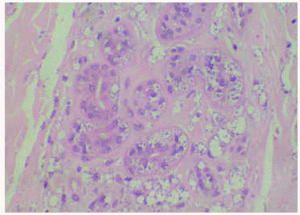

La biopsia cutánea mostró una epidermis con hiperqueratosis homogénea sin paraqueratosis y mínimo infiltrado inflamatorio. Se observaban múltiples amastigotes en el interior de los queratinocitos, con degeneración vacuolar y libres a todos los niveles de la epidermis, incluyendo la capa granulosa y entre la queratina de la capa córnea. También se observaron en menor proporción en el conducto excretor ecrino y en el acrosiringio. En la dermis y la hipodermis se apreciaban múltiples organismos intra y extracelulares, entre los haces de colágena, alrededor de las glándulas ecrinas, entre los adipocitos y alrededor de los vasos sanguíneos (figs. 2 y 3).

Fig. 3.--Abundantes amastigotes en las glándulas y ductos ecrinos. (Hematoxilina-eosina, x400.)